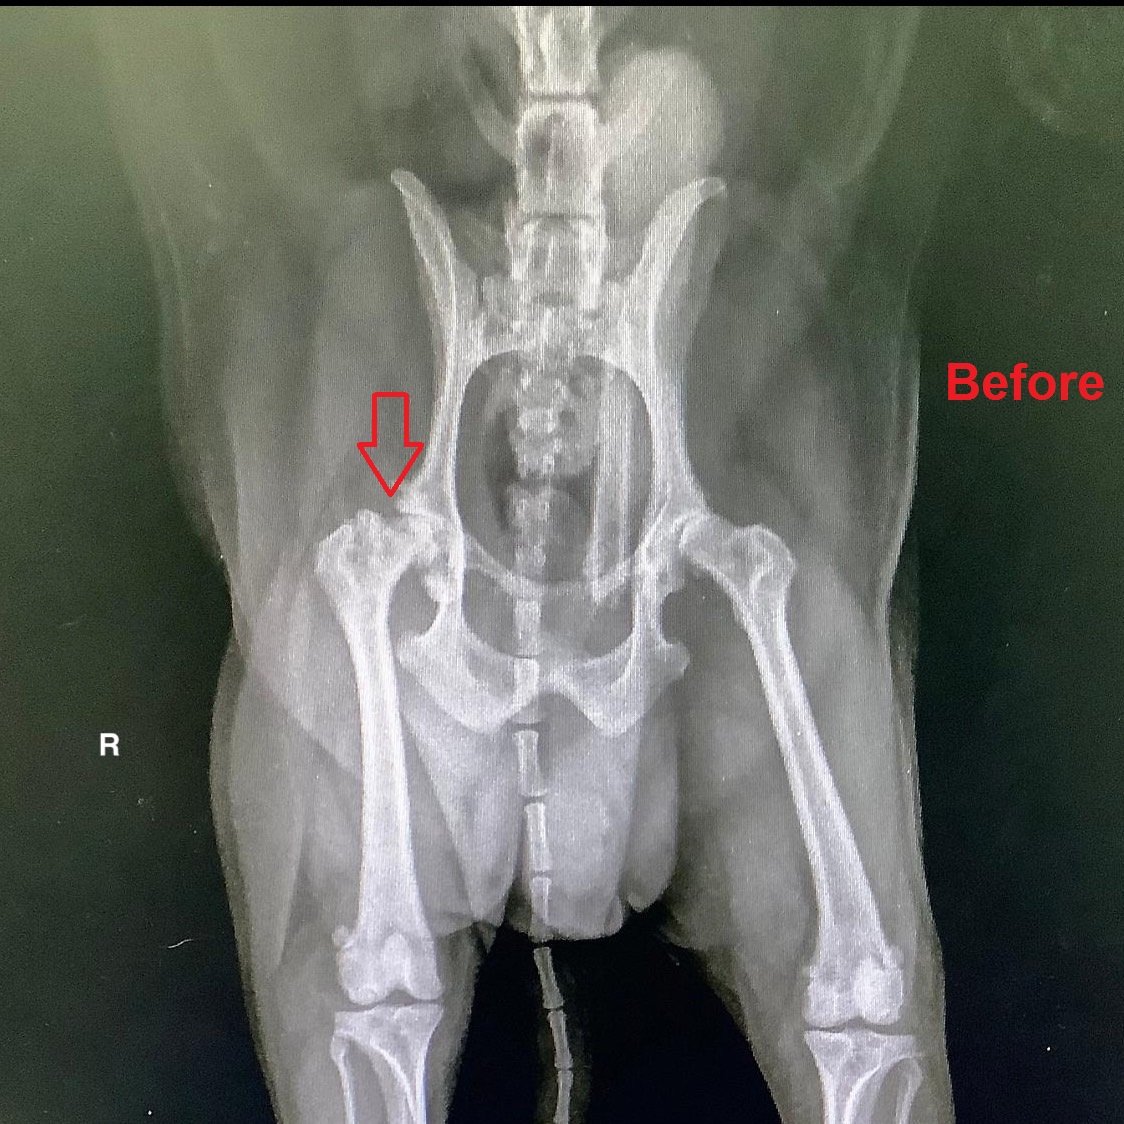

สัตวแพทย์ตรวจร่างกายเบื้องต้นพบว่า โมจิมีเห็บหมัดบนร่างกาย เสียงหัวใจเริ่มผิดปกติ ขาหลังขวาลงน้ำหนักไม่ได้ คลำพบการเคลื่อนของข้อสะโพกขวา กล้ามเนื้อขาหลังขวาเริ่มมีการฝ่อลีบจากการที่ไม่ใช้ขาเป็นเวลานาน สัตวแพทย์จึงตรวจวินิจฉัยเพิ่มเติมด้วยการตรวจเลือดพบว่าโมจิติดเชื้อพยาธิเม็ดเลือดชนิด Ehrlichia canis ซึ่งโน้มนำให้มีภาวะเกล็ดเลือดต่ำร่วมด้วย และเมื่อถ่ายภาพเอกซเรย์พบว่ากระดูกข้อสะโพกขวาเคลื่อนหลุดจากเบ้า

น้องโมจิได้รับการผ่าตัดโดยสัตวแพทย์ผู้เชี่ยวชาญด้านโรคกระดูกและข้อ โดยใช้เทคนิค Femeral head and neck excision หรือ FHNE ซึ่งเป็นการตัดเอาส่วนหัวและคอของกระดูกขาหลังส่วนต้นออกเพื่อลดการเสียดสีของหัวกระดูกกับเบ้ากระดูกเชิงกราน หลังจากนี้ร่างกายจะสร้างเนื้อเยื่อพังผืดเข้ามายึดเป็นข้อเทียมทดแทนส่วนที่ตัดออกไป การผ่าตัดเป็นไปได้ด้วยดี น้องโมจิฟื้นตัวไว และอยู่ดูแลภายหลังผ่าตัดที่โรงพยาบาลสัตว์ไอเว็ทจนตัดไหม ตอนนี้น้องโมจิเริ่มลงน้ำหนักที่ขาหลังขวาได้แล้ว แต่ยังคงต้องเข้าหน่วยกายภาพบำบัดเพื่อฟื้นฟูกล้ามเนื้อที่ฝ่อลีบให้กลับมาแข็งแรง และช่วยให้สามารถเดินได้ใกล้เคียงปกติที่สุด